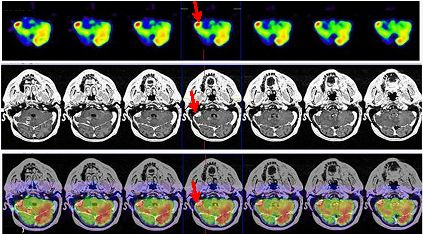

La terapéutica tras el estudio PET-RNM cerebral consistió en radiocirugía, utilizando la Guía de Estereotaxia Brainlab, imágenes de fusión RNM-CT para planificación, fotones de 6 MV con técnica de arcoterapia dinámica conformada con un microcolimador multilámina Brainlab, administrando una dosis máxima de 22 Gy en la lesión temporal derecha, una dosis de 20 Gy al margen de la lesión, 0,8 Gy en las vías ópticas, 7 Gy en troncoencéfalo y 1,4 Gy en quiasma. La RNM cerebral de control mostró cambios postratamiento en la zona más caudal del lóbulo temporal derecho. Al cabo de 3 años, el paciente refiere cefalea aguda, discreta bradipsiquia y alteración de la marcha por hemiparesia izquierda. La RNM informa persistencia tumoral en región mesial posterior temporal derecha con infiltración en región más posterior del lóbulo temporal que afecta y atraviesa el tentorio, con compromiso del lóbulo cerebeloso derecho. Un estudio PET-RNM cerebral confirma la recurrencia tumoral (fig. 2).

Tras los hallazgos del PET-RNM cerebral actual, se procede a tratamiento radioterápico estereotáxico fraccionado, abarcando las lesiones hipermetabólicas, con fotones de 6 MV con técnica de arcoterapia conformada dinámica con un microcolimador multilámina, a razón de 4,5 Gy/día, 5 días a la semana hasta alcanzar una dosis total de 17 Gy. La RNM de control mostró cambios postratamiento en la zona más profunda del lóbulo temporal derecho, áreas de necrosis y hemorragia interna en el ángulo pontocerebeloso derecho.